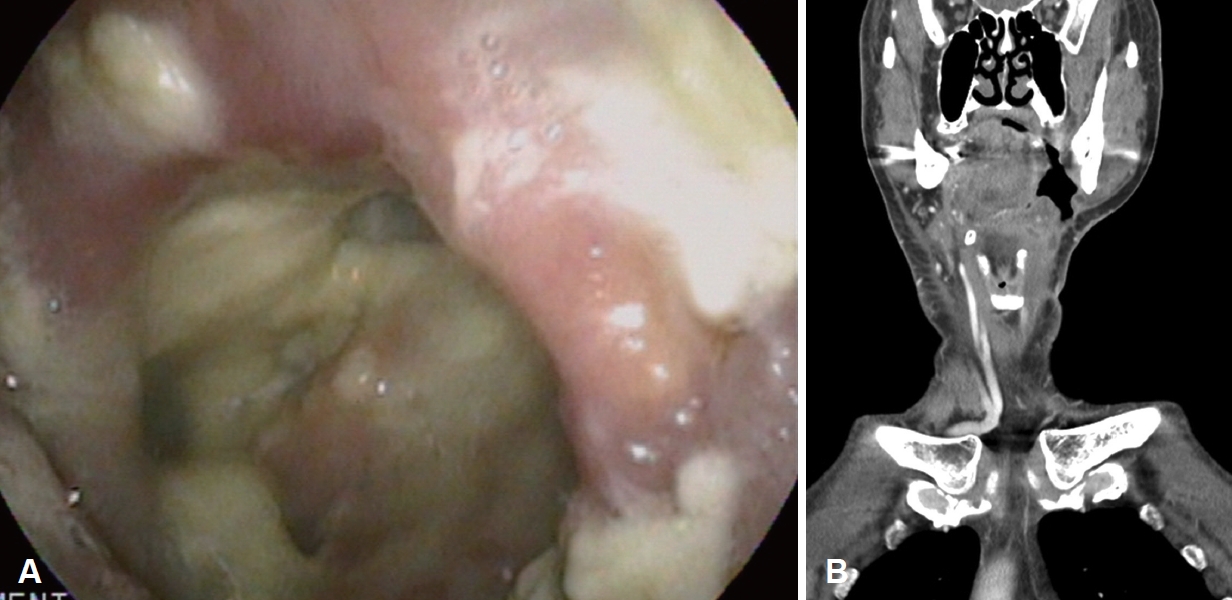

환자는 술후 동시항암방사선 치료 종료 6주 후부터 호흡곤란 증상을 호소하여 방사선으로 인한 후두염 진단하에 3차례 입원 후 보존적인 치료를 하고 퇴원하였다. 이후 정기적 외래 추적 관찰 중 술후 동시항암방사선 치료 종료 후 21주째, 좌측 경부 level II에 작은 피부 결손 부위와 함께 혼탁성삼출물이 흘러나오는 것을 발견하였고, 당시 시행한 경부 전산화단층촬영 검사에서, 이전에는 보이지 않던 좌측 편도와에서 좌측 부인두공간으로 연결된 누공이 새로 형성된 것을 확인하였다(Fig. 3). 이에 따라 국소마취하 절개 배농술을 시행한 뒤, 피부 결손 부위에서 구인두 공간까지 이어지는 누공길(fistulous tract)을 확인한 이후, 배액관의 도관을 재단하고 경부에서 구인두 방향으로 이를 거치하여 지속적 음압 드레싱을 시행하였고, 이와 함께 비영양관 튜브를 통한 식사 및 정맥 내 항생제 치료를 시행하였다(Fig. 4). 치료를 유지하여 1달 뒤 시행한 경부 전산화단층촬영 검사에서 인두피부누공이 호전되지 않은 것을 확인하였고, 이에 따라 전신마취하 대흉근피판을 이용하여 결손 부위를 재건하였다(Fig. 5). 수술후 8일째 금식과 정맥 내 고영양 치료를 유지하던 중, 환자가 협조하지 않아 소량의 경구식이를 시작하였다. 수술 후 12일째 수술 부위 배액관을 통해 다시 타액이 유출되는 것을 확인하여 전신마취하에 경부 탐색술을 시행하였고, 피판 부위는 유지되고 있는 것을 확인하여 죽은조직제거술을 시행한 후 수술을 종료하였다. 환자는 금식을 다시 유지하였고 대흉근 피판재건술 이후 38일째 식도조영술을 시행하였으며, 좌측 이상와 부위에서 작은 누공이 추가로 확인되었으나(Fig. 6), 환자가 경구식이를 강하게 희망하여 2일 후 소량의 경구식이를 재개하였다. 이후 배액관의 배액량이 줄어드는 양상을 보이는데다 환자가 외래 통원치료를 희망하여 입원한 후 80일만에 배액관을 유지한 채로 퇴원하였다.

퇴원 이후 3주째 외래에서 추적 관찰 중, 신체 진찰상 첫 누공 발생 부위와 별도로 좌측 쇄골상 경부 부위의 발적 및 부종이 발견되어 시행한 세침 흡인상 혼탁한 배액이 확인되었다. 전신마취하 경부 탐색술을 시행하였고, 경구강을 통해 인두 부위를 확인하였지만 구인두 부위에는 누공이 의심되는 소견은 보이지 않았다. 피부쪽 누공 입구를 통해 배액관을 삽입 후 지속적인 음압을 유지하며 드레싱 치료와 항생제 치료, 정맥 내 고영양 치료를 시행하였다. 수술 후 8일째 경구식이를 시작하였고, 9일째 식도조영술을 시행한 결과 좌측 이상와의 누공과 함께 동측의 편도와 부위의 작은 누공 입구가 아직 확인되었다(Fig. 7). 수술 후 13일째 압박드레싱을 유지한 채로 퇴원하였다.